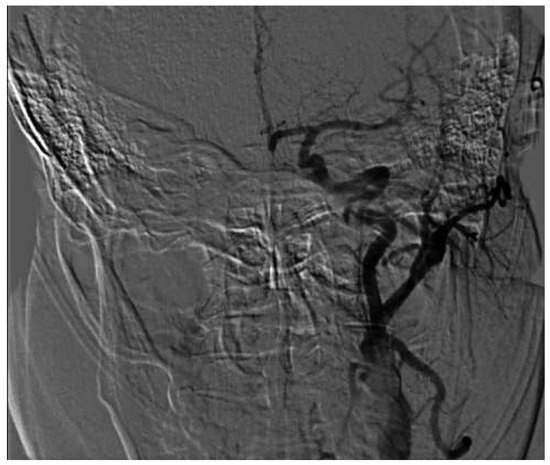

Mechanical Thrombectomy After Embolic Internal Carotid Artery Occlusion in Acute Stroke

Case presentation